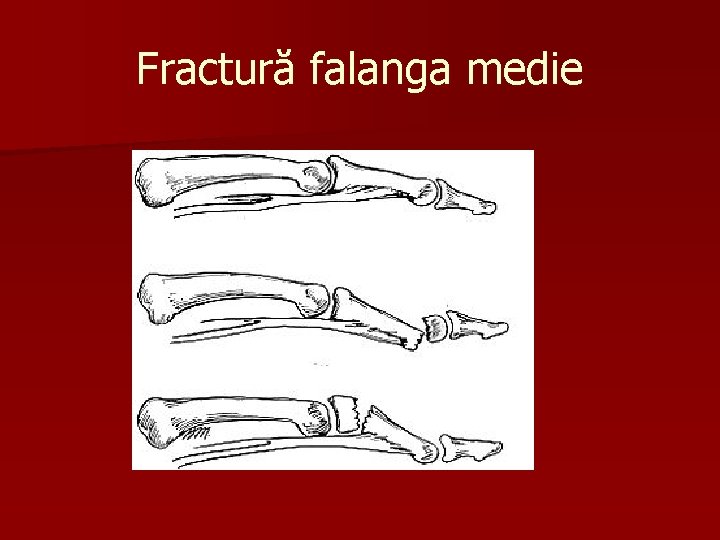

Fractură falanga medie